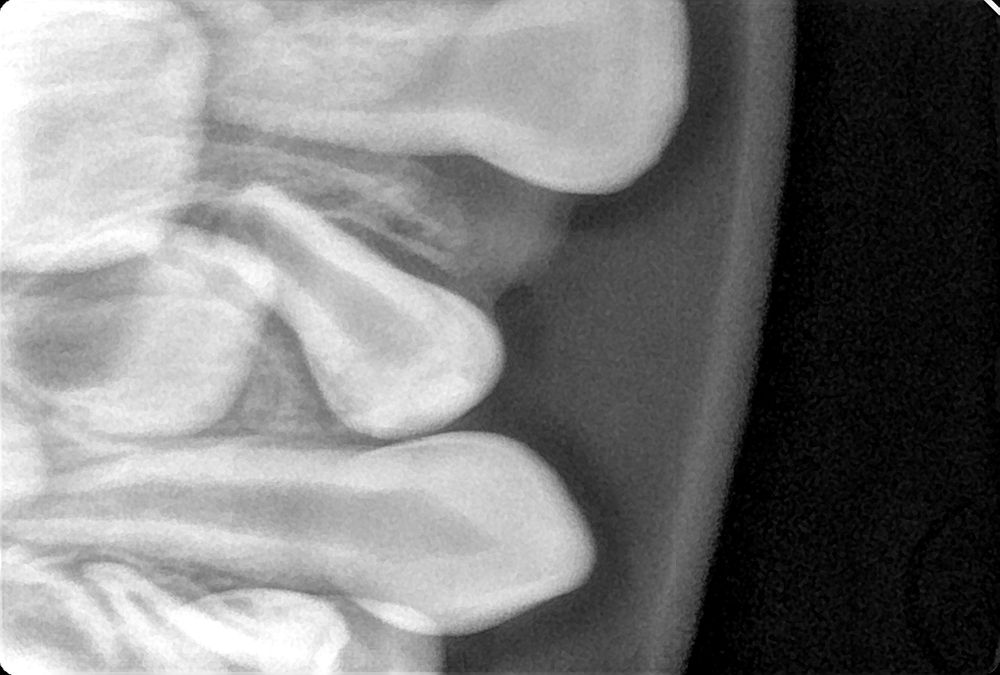

Вколотил молочный зуб ( фото не для слабонервных)

ЗубкиВсем привет. Просто хотела спросить опыт, так как ждём завтрашнего дн. Сын 2.9 ударился и вколотил молочный зуб. Вошел очень криво и назад,. Сегодня врач сказала, что надо удалять.( Это врач не наша, только дежурную нашла 9 мая). Завтра буду звонить нашей. Может кто сталкивался, что обычно делают?

У моей дочери был вколоченный вывих переднего центрального резца в 1,7.Как не пытались, даже рентген не смогли сделать в том возрасте,но мы обратились срочно к дежурному врачу, поскольку был выходной, потом для перестраховки ещё к одному стоматологу возила.В первые дни, пока шла кровь, врач назначал антибиотик.

Крови было много, разорвала ещё верхнюю уздечку,зуб вошёл внутрь хорошо.

Врач сказал будем наблюдать, ведь рентген не сделали.Поначалу зуб немного шатался, припухлость была,а потом сам прирос,и вот уже полтора года зуб на месте, беленький,хотя стоматолог давал плохие прогнозы,что потемнеет, будет болеть и тд.

Поэтому могу сказать,что вколоченный зуб не всегда равно удаление,но по снимку ничего не скажу.